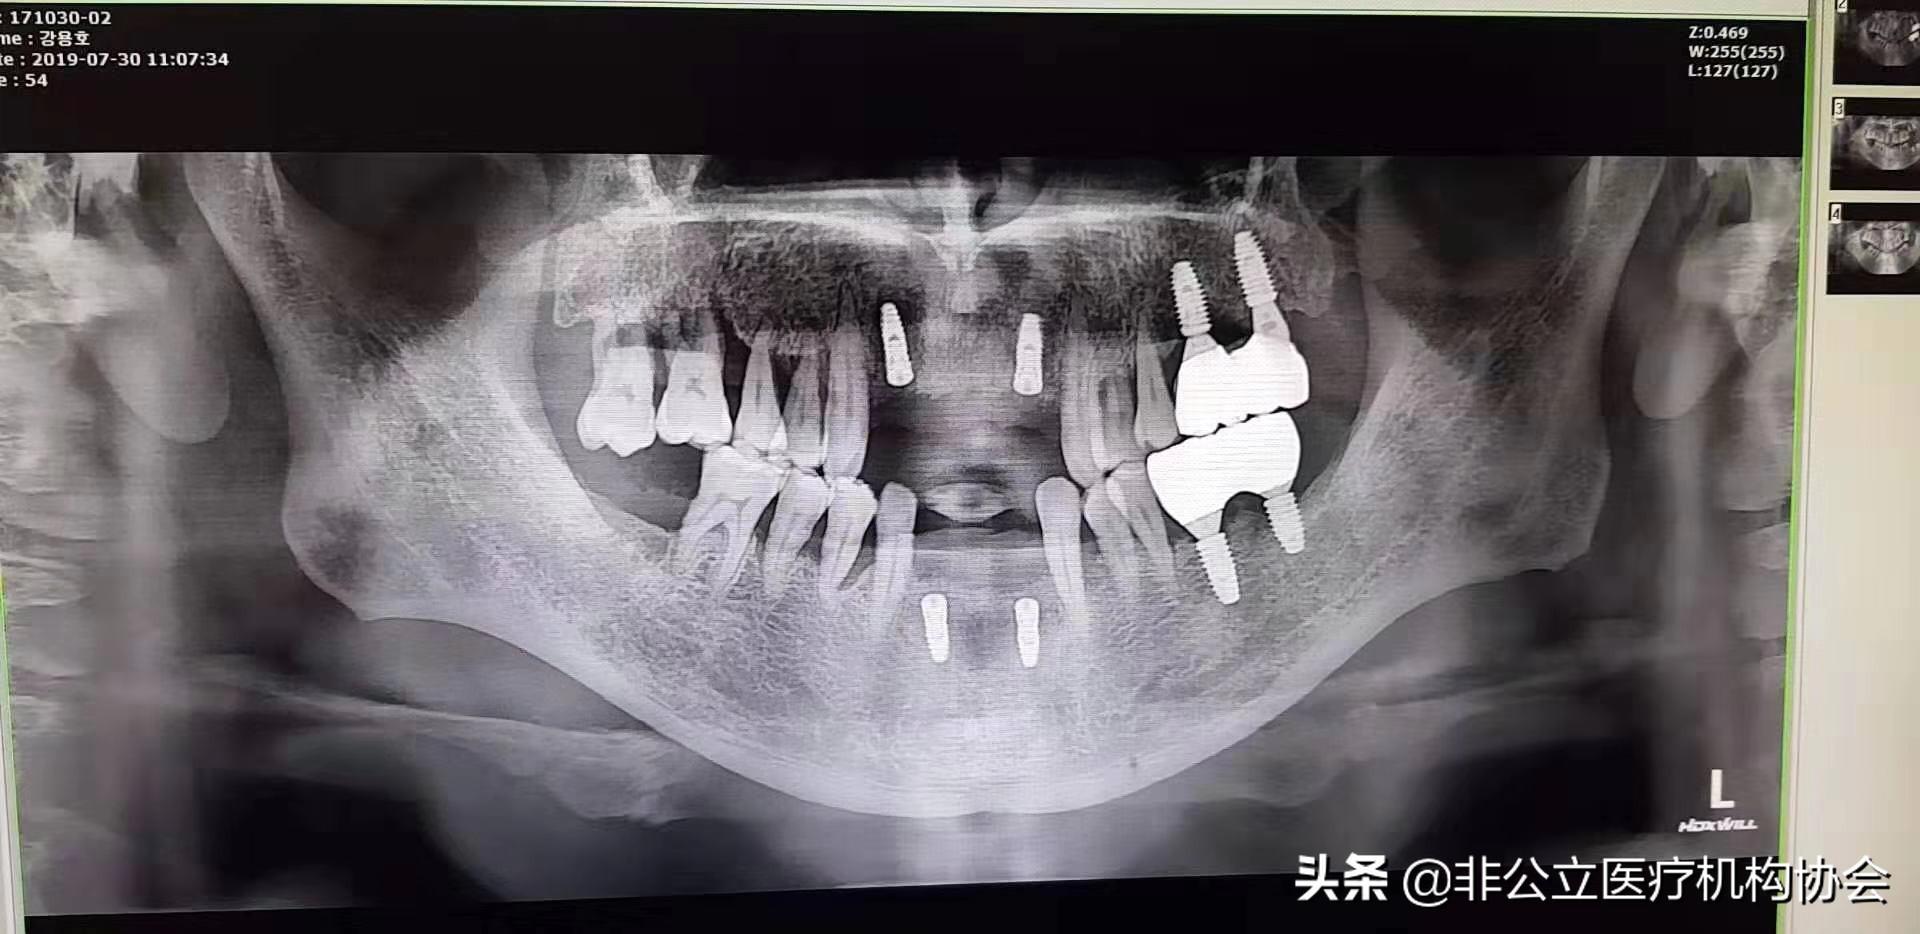

54歲患者術后X光照片

患者第二天來診所復診,上下頜恢復好,有一點輕微腫。

此病例第題部分修復完畢,一般經過3~6個月的愈合時間,骨與種植體結合,義齒便可修復在種植體上制作完成了。